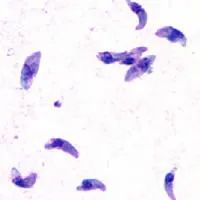

弓形虫,乍一听名字,可能会让人觉得是一种长得像弓的虫子,像条蛔虫或者蚯蚓那样蠕动。其实,弓形虫个头小得多,它是一种单细胞寄生虫,长 3.5~6.5μm,宽 1.5~3.5μm,比起弓,它的形状更像是香蕉。

弓形虫显微图(图片来自wiki)